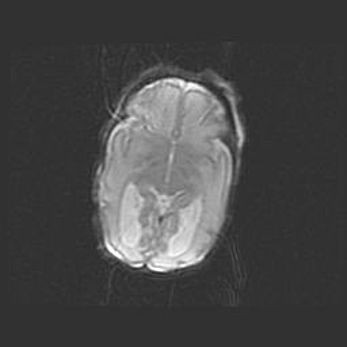

Мальформация Денди-Уокера. Киста задней черепной ямки.

Агенезия мозолистого тела.

Возраст: 2,5 месяца

Вес: 2420 г

Пол: женский

Окружность головы: 37 см

Срок гестации: 32 недели

Мальформация Денди—Уокера — редкий вид патологии ЦНС, представляющий собой врожденный порок развития каудального отдела ствола и червя мозжечка, ведущий к неполному раскрытию срединной (Мажанди) и латеральных (Лушка) апертур IV желудочка мозга. Для этогно синдрома характерна триада симптомов: гипотрофия червя мозжечка и/или полушарий мозжечка, кисты задней черепной ямки, гидроцефалия различной степени. В 70% случаев порок сочетается и с другими аномалиями головного мозга, в частности с агенезией мозолистого тела.